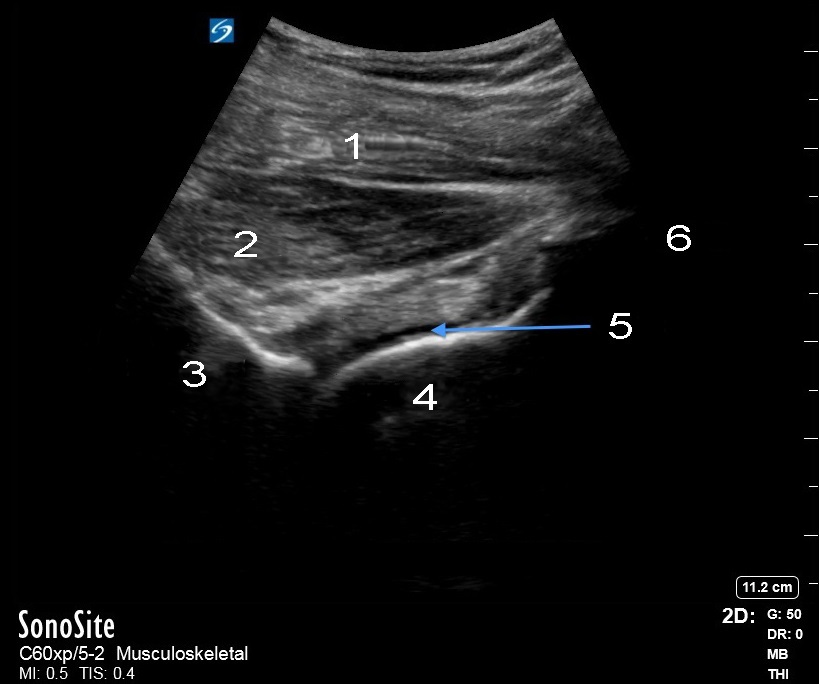

Hip Lateral Joint Recess Image

1. Gluteus Medius

2. Gluteus Minimus

3. Lateral Acetabulum

4. Femoral Head

5. Recess

6. Trochanter